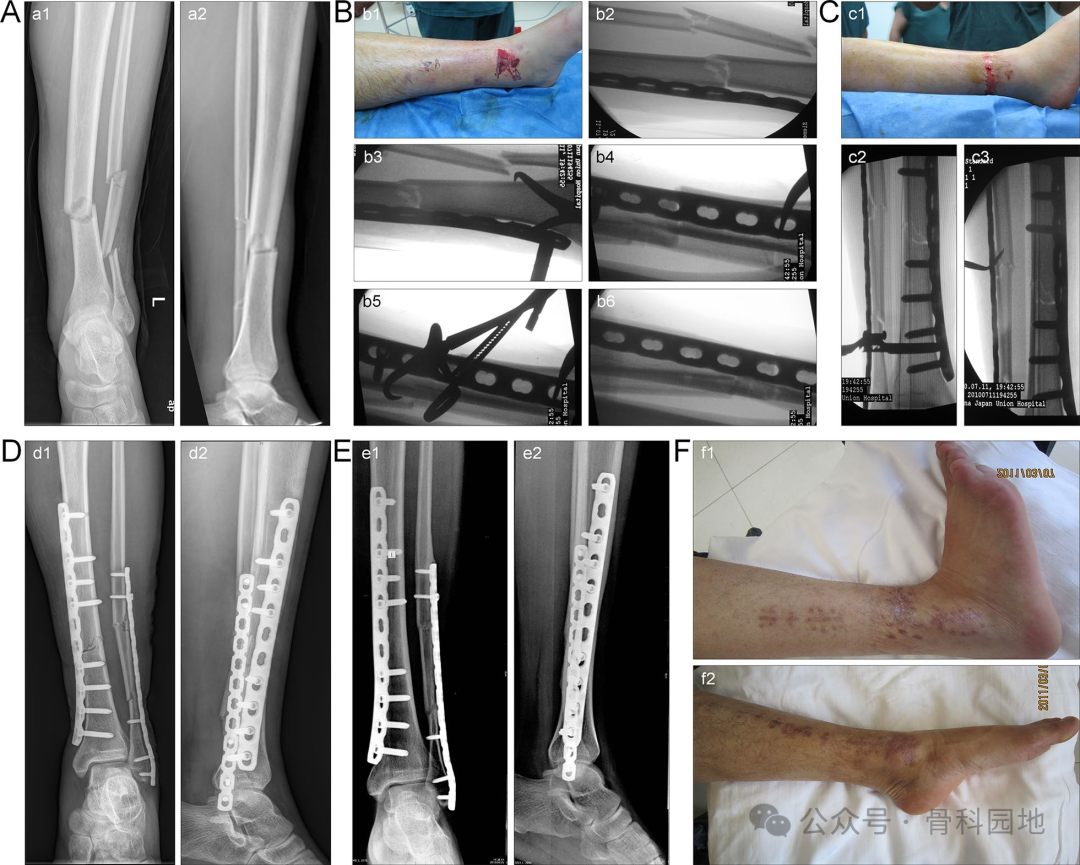

在短斜骨折和横骨折中,传统的经皮夹持技术通常难以达到满意的复位。然而,当钢板提供正确的对准时,骨折的一端可以首先复位并通过经皮夹持暂时固定。然后,在另一个复位钳的钳夹下完成准确的复位(图)。

前外侧钢板辅助经皮钳夹复位治疗多段骨折。